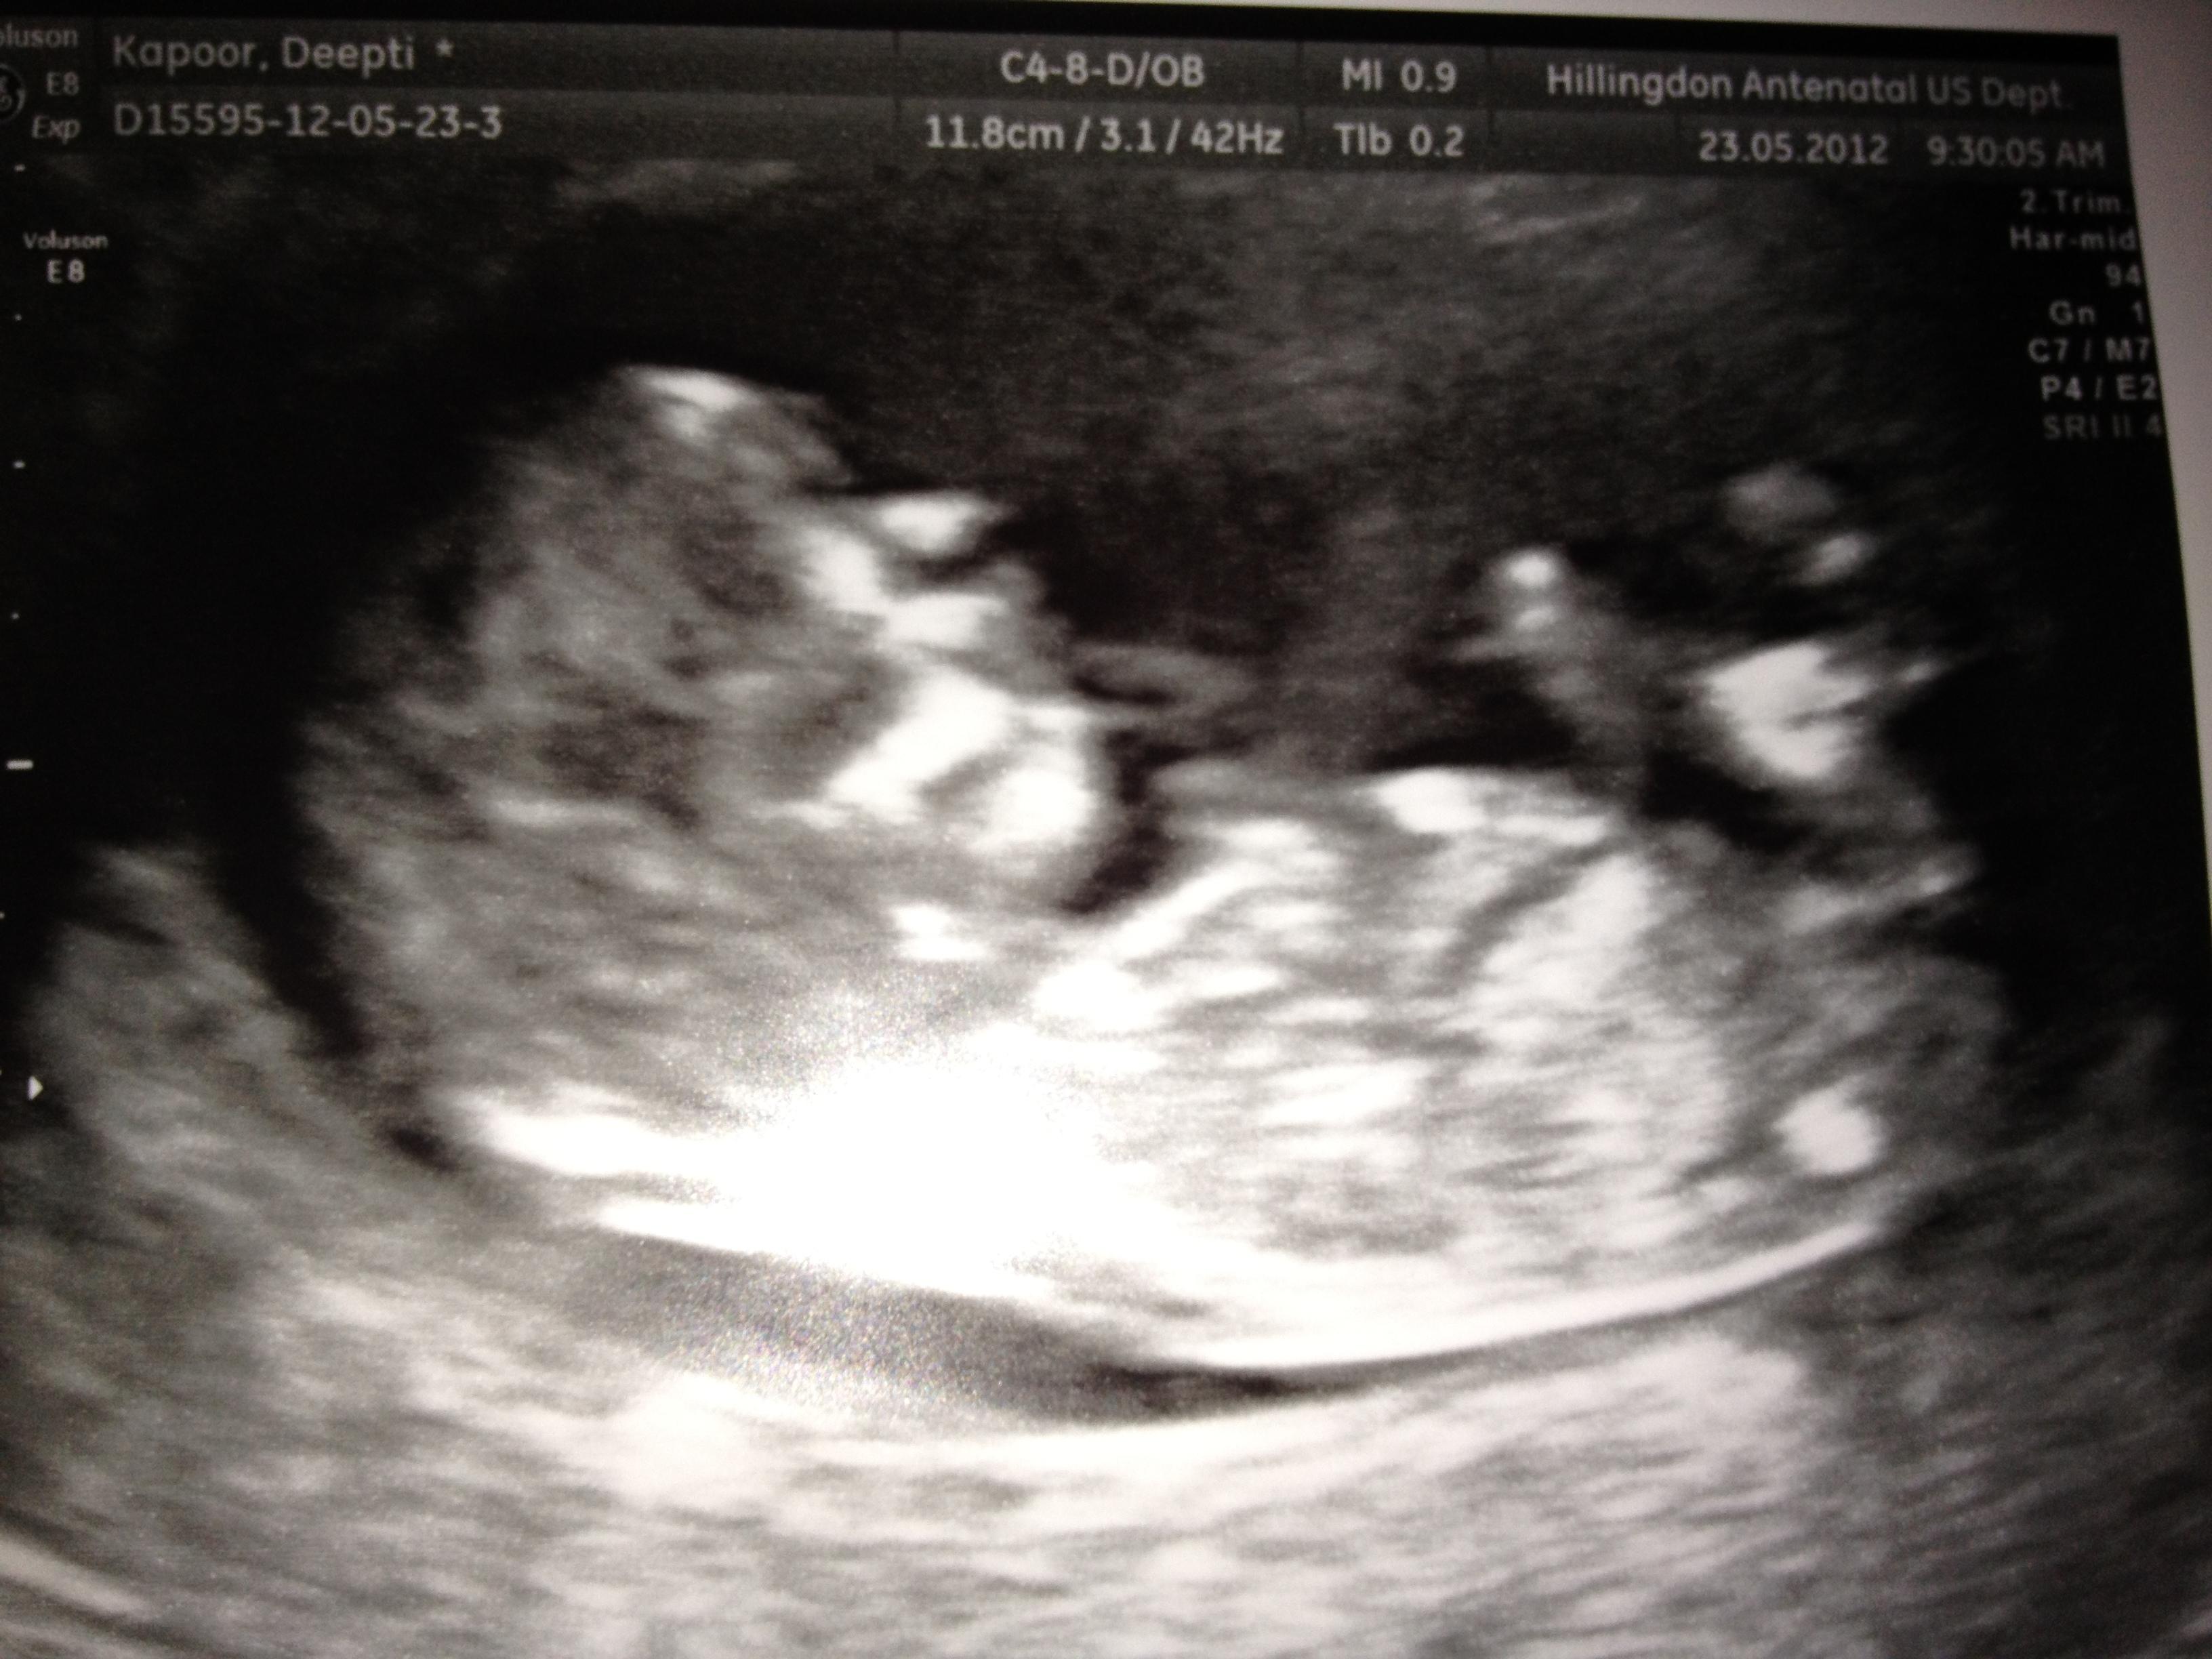

(Deepti's angel has arrived)

" Me and my husband tried for at least 18 months for a baby with no joy. We even followed all the guidance published under the sun on how to get pregnant. This included expensive fertility monitors, vitamins etc. I then came across an article on the benefits of accupuncture and found out about Dr Fang. I booked an appointment and was told that with accupuncture and Chinese medicine it could take between 3 to 6 cycles to get pregnant. I had a stressful job and with accupuncture I felt it helped me become less anxious and helped me feel relaxed. I Also started charting my temperature and noticed overtime my chart was getting more regular with a combination of accupuncture and Chinese medicines. After 3 full cycles I found out I was pregnant and was overjoyed that it finally happened after so long. I am still taking accupuncture and have so far had a pretty normal pregnancy without morning sickness.

Thanks to Dr Fang. "

Deepti, Uxbridge